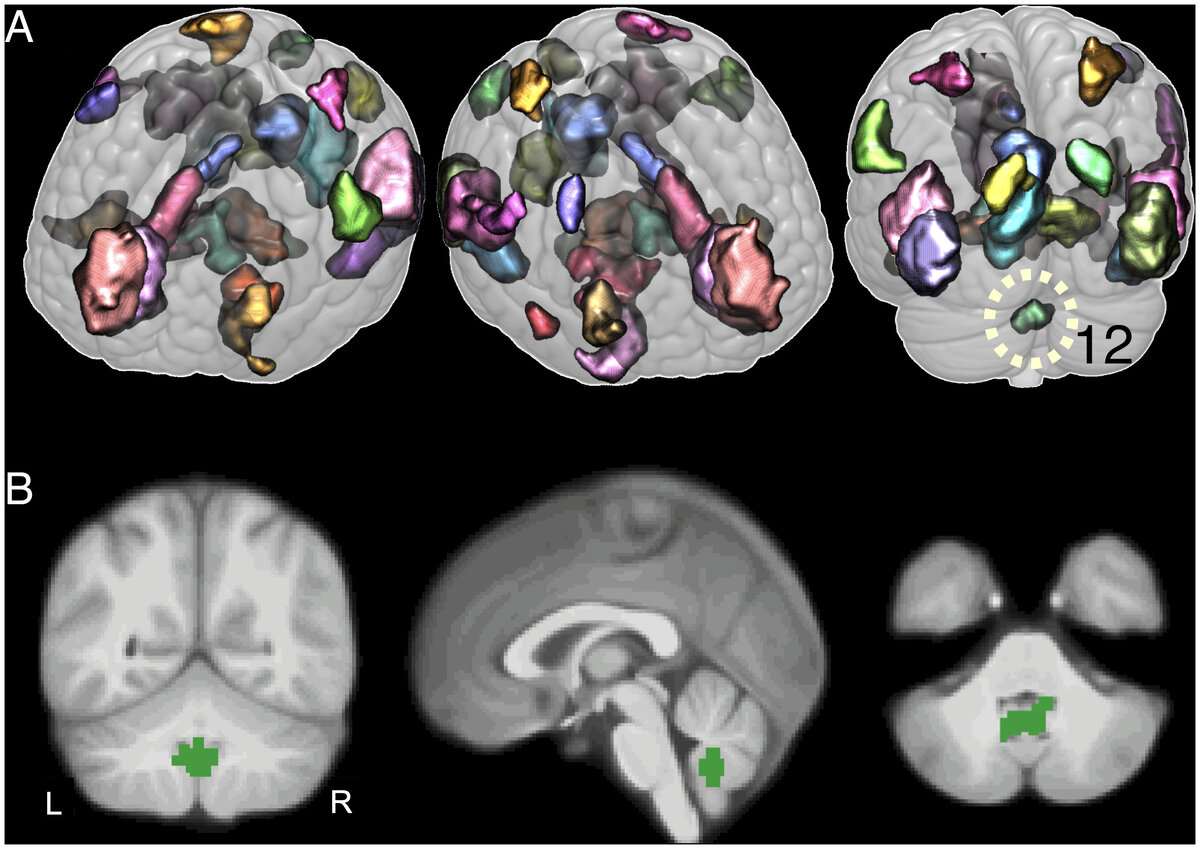

Текущее исследование под руководством профессора Доминика де Кервена (Dominique de Quervain) и Андреаса Папассотиропулоса (Andreas Papassotiropoulos) из Базельского университета (University of Basel) изучило роль мозжечка в хранении эмоциональных переживаний. В крупномасштабном исследовании ученые показывали 1418 участникам эмоциональные и нейтральные изображения и анализировали активность их головного мозга с помощью магнитно-резонансной томографии.

Положительные и отрицательные образы запомнились участникам гораздо лучше, чем нейтральные. Хранение эмоциональных образов было связано с увеличением активности в тех областях головного мозга, которые уже до этого были известны. Однако команда также выявила повышенную активность и в мозжечке.

Исследователи также смогли продемонстрировать, что мозжечок имеет более сильную связь с различными областями головного мозга в процессе усиленного хранения эмоциональных образов. Мозжечок получает информацию от поясной извилины — области мозга, играющей важную роль в восприятии и оценке чувств. Кроме того, мозжечок посылает сигналы в различные области мозга, включая миндалевидное тело и гиппокамп. Последний играет центральную роль в хранении памяти.